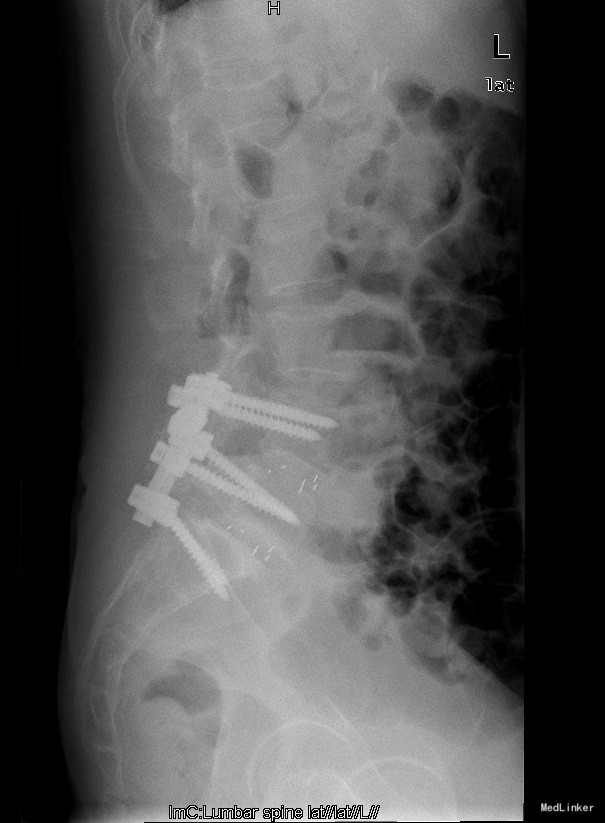

诊断:腰4椎II°滑脱症,腰5椎I°滑脱症 治疗:经后路腰4、5椎切开复位、椎管减压、Capstone椎间及后外侧人工骨+自体骨植骨融合、Legacy内固定术